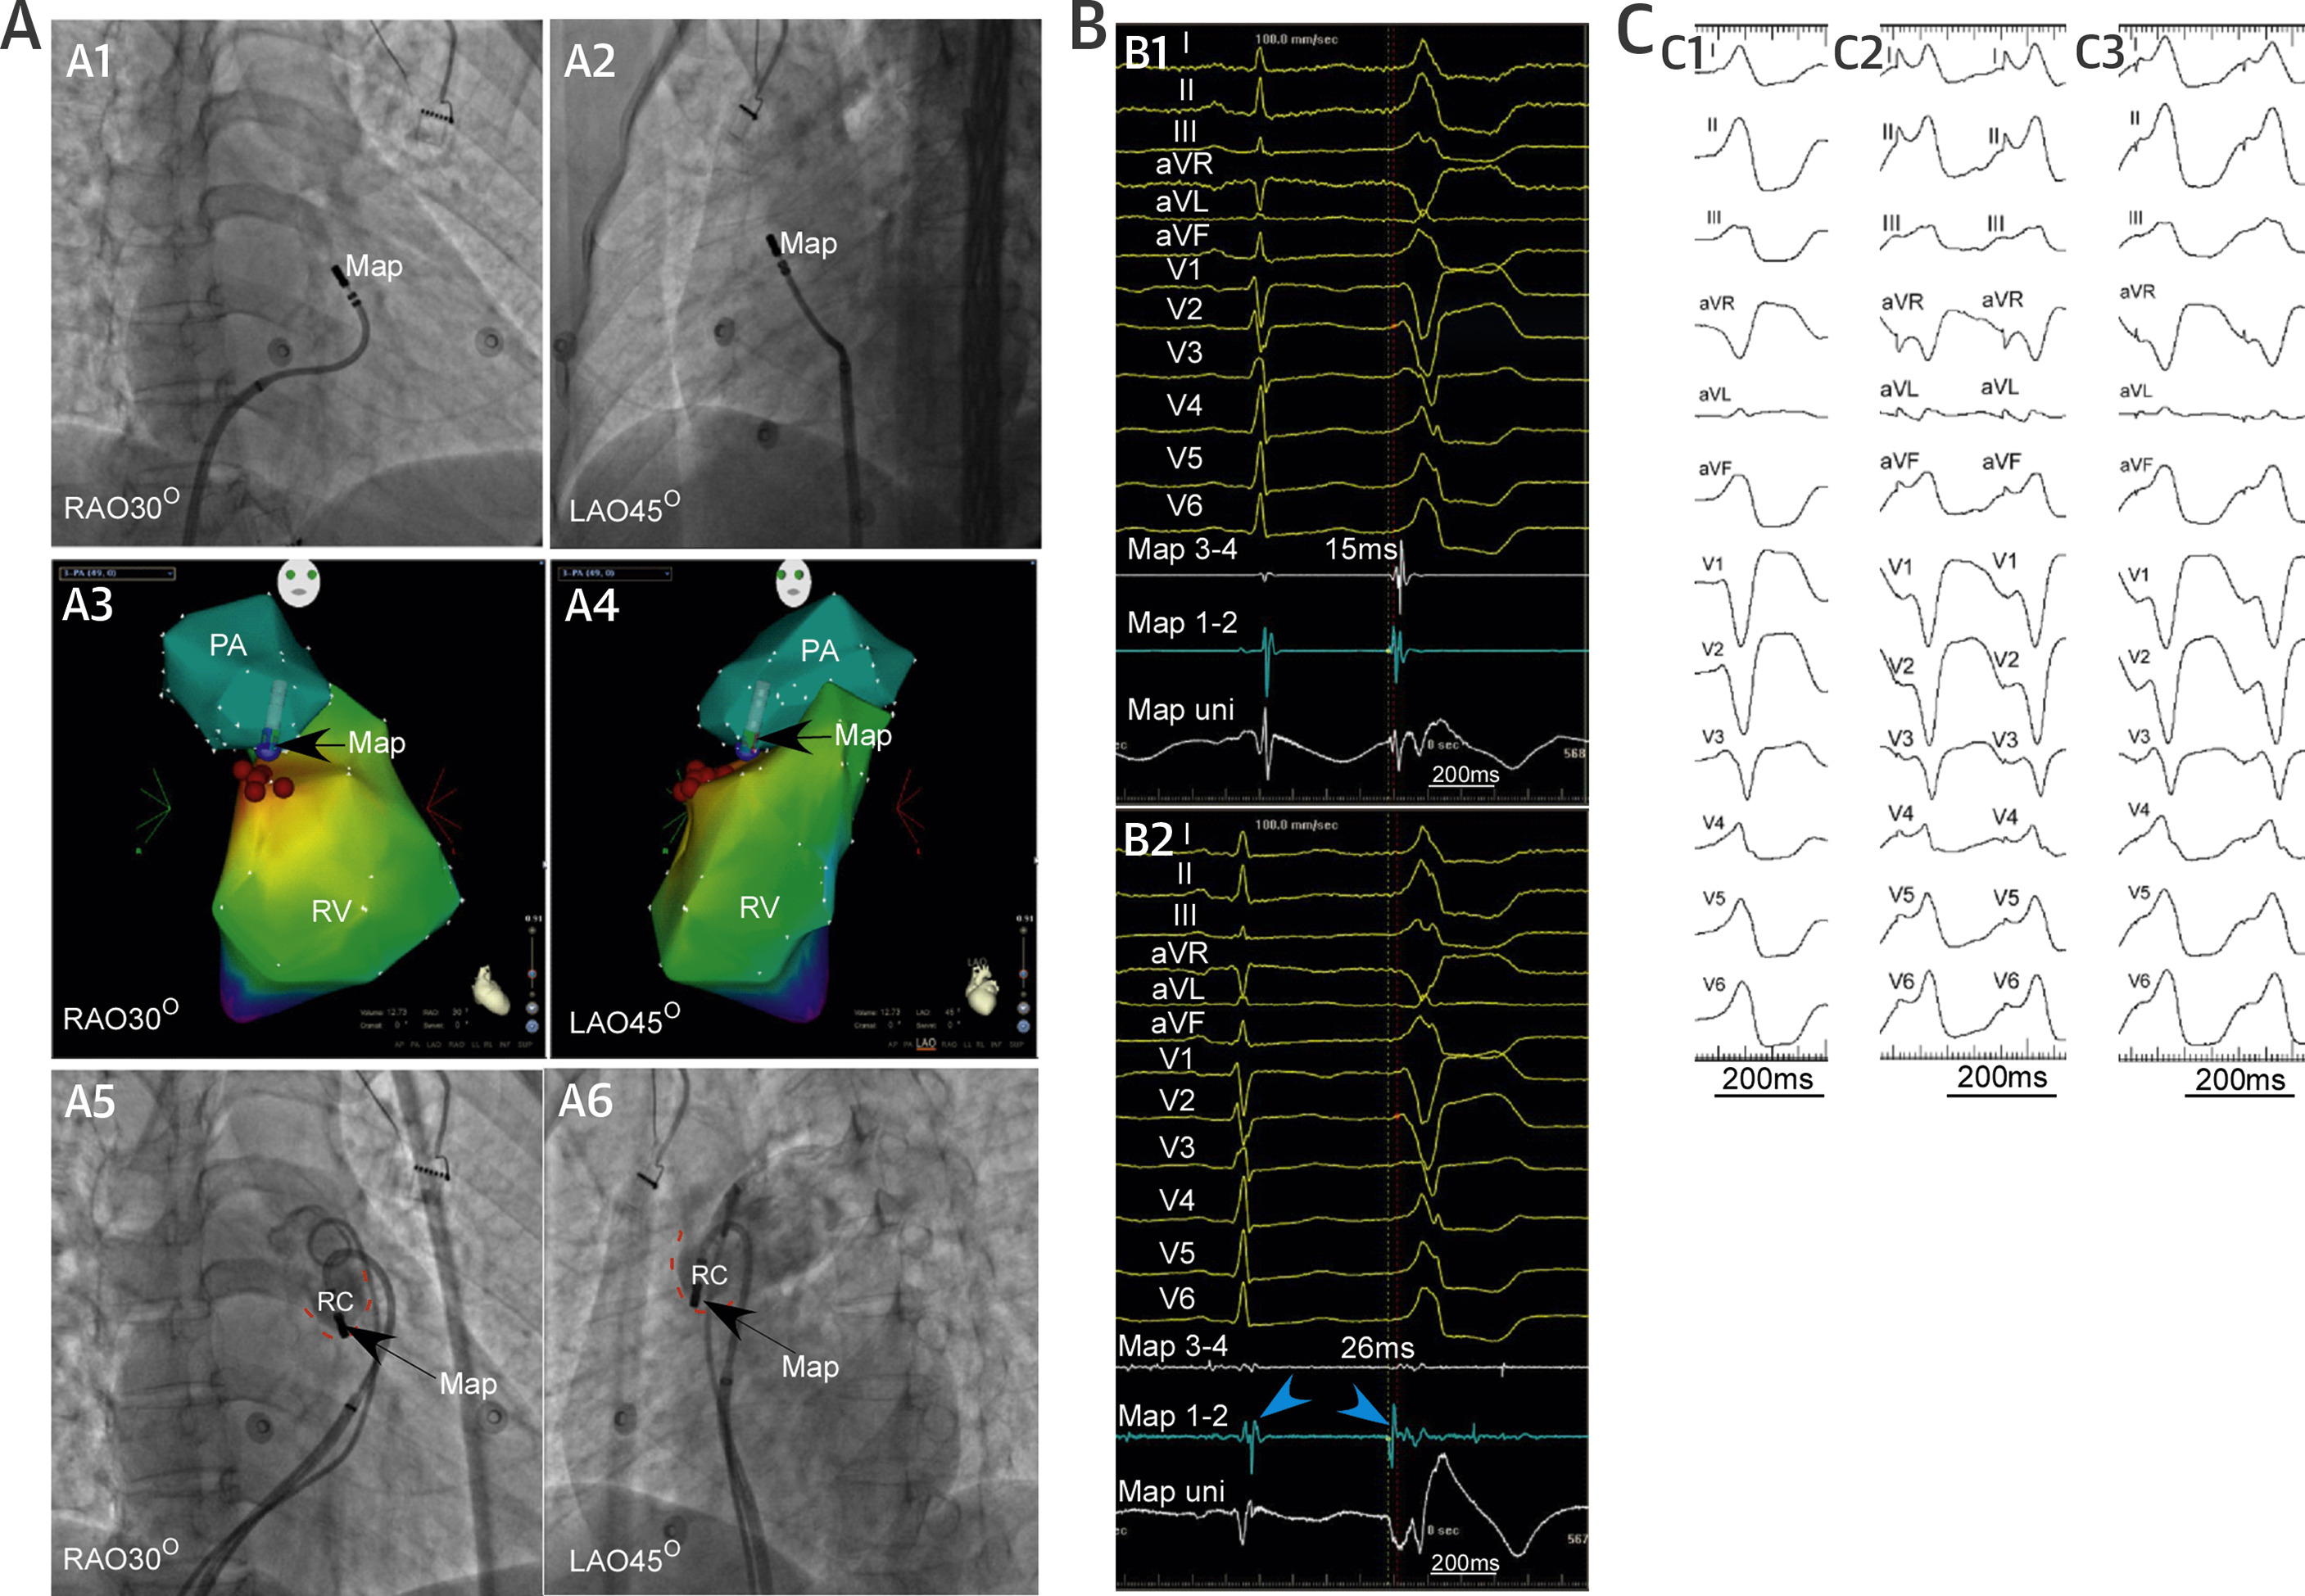

Pulmonary sinus cusp VT

pulm_cusp.jpg

Liao Z, Zhan X, Wu S, Xue Y, Fang X, Liao H, et al. Idiopathic ventricular arrhythmias originating from the pulmonary sinus cusp: Prevalence, electrocardiographic/electrophysiological characteristics, and catheter ablation. J Am Coll Cardiol 2015; 66: 2633–2644.

Suspect when unsuccessful in high RVOT

psc_site.jpg